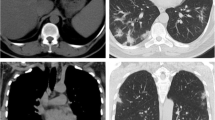

For this study, we chose to perform only a single measurement using a liver attenuation value ≤ 40 HU, since the comparison of hepatic attenuation with splenic attenuation is a more complex method, requiring more time, effort and possibly not contributing to accurate prediction of fat content [17]. The measurement in the liver was performed at just one slice level. This is supported by data showing that fat deposition in the liver is relatively homogeneous and most of the variation in the measurement of attenuation in this organ can be captured by measuring it at just one slice [18]. In this study we sought for more homogeneous areas of the liver parenchyma, avoiding vessels, biliary tree or focal lesions [16]. In order to do that, we chose to place the single ROI measurement—with an area of approximately 10cm2–in the right liver lobe, preferentially between the segments VI and VII, because it could proportionate the more suitable area with these characteristics for evaluation (Fig. 1).

Imaging analyses were performed by two readers (Readers 1 and 2, with 5 and 3 years of experience in abdominal imaging, respectively), who were blinded to clinical and laboratory data of all individuals and not involved with patients’ selection. Each reader evaluated a portion of the cohort (Reader 1, 121 cases and 61 controls; Reader 2, 83 cases and 51 controls).